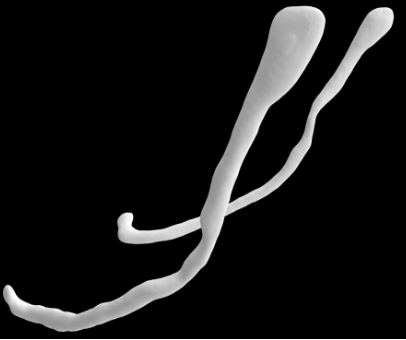

Cone-beam computed tomography (CBCT) is a commonly used imaging technique in dentistry that generates images using a fan-shaped beam of X-rays.10 Cone-beam computed tomography produces high-resolution images that can be reconstructed into a 3D image, rendering it a valuable tool for evaluating facial anatomy, including the IAC and its variations.11, 12, 13 Ozturk et al. identified 3 distinct configurations for the IAC within the mandible (Figure 1).14